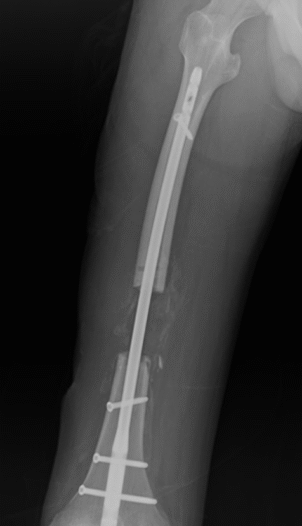

Una fractura es la rotura en un hueso, muy frecuente tras golpes, caídas o accidentes.